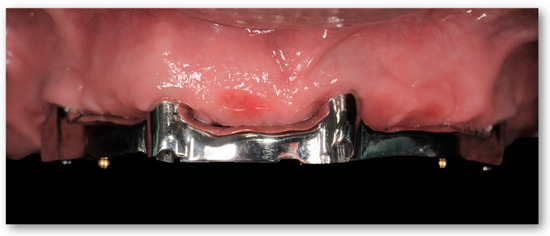

2.2. Second Step: From FDP to Implant-Supported Overdenture